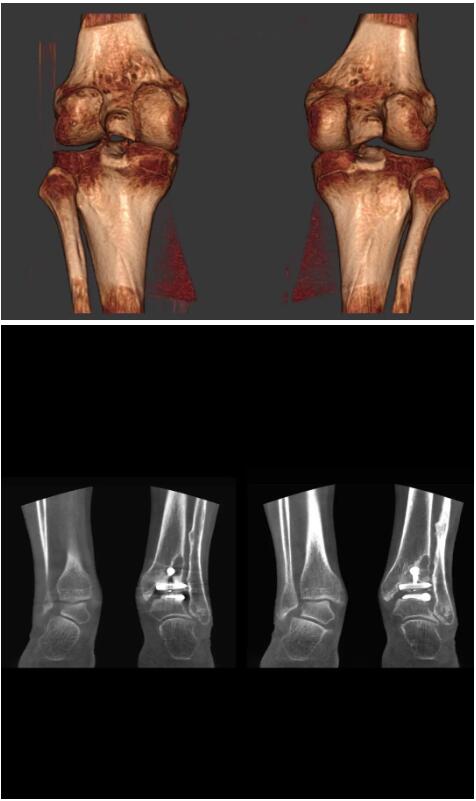

另外一款被稱為世界上最小的CT,它的重量僅300磅,不僅能夠掃查足部,還可以檢查膝蓋和上肢等。

這款CT使用非常方便,通過上下移動保持與患者的手臂或者雙腿齊平,掃描快速,僅需要30秒左右就可以完成掃查。

以上介紹的CT均來自國外同一家公司,這些CT均配置了可視化軟件,可以進行切片、3D重建以及大型CT附帶的所有典型的操作功能。

以下是這些“特立獨行”的CT所拍出來的圖像: